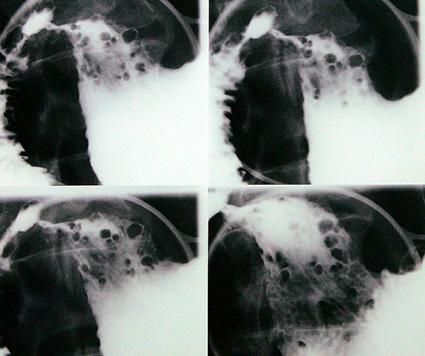

clasificación del pacienteTumor Maligno del Sistema Linfático/Linfoma Maligno

parte(separada por órganos)estómago(región)/antro

método de exámenRayos X

clasificación ectoscópica de tumoresTipo 0(tipo superficial)/Tipo IIc(IIc)

diámetro mayor del tumor40 -

grado de penetraciónsm